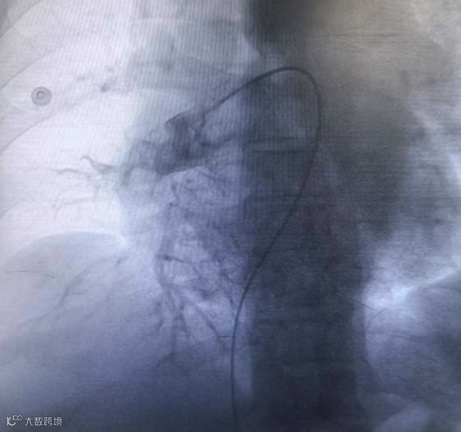

复查造影提示左右肺动脉闭塞段复通,血栓负荷明显减少,继续予以后续抗凝治疗。

术后造影